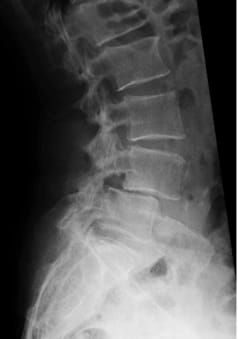

Compared to other implants, the viscoelastic disc prosthesis has the advantage that its design perfectly mimics the function of the natural disc. Furthermore, extensive laboratory testing has proven that it has a durability of at least 50 years. Whether and how surgical treatment of the affected vertebral segments should be carried out is planned individually by the specialist after thorough diagnosis (MRI, CT, X-ray, physical and neurological examination). If, for certain reasons, partial fusion of a section of the spine is unavoidable, this should be limited to one segment as far as possible, as shown in the following example. In this way, the greatest possible functionality of the spine can be maintained or restored.

Postoperative status: Complete axial correction of the lumbar spine with two disc prostheses and a PEEK cage. Normal lordosis of the lumbar spine also visible in the lateral view after the operation. (Spine Centre Rischke)